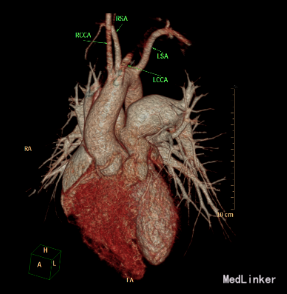

心脏CT:内脏、心房正位,左位心。肺动脉瓣二叶瓣,左室发育好。McGoon指数3.9。左室容积指数69.6ml/㎡。干下室间隔缺损,缺损约21.8mm。右位主动脉弓。迷走左锁骨下动脉。左锁骨下动脉异常起源于降主动脉起始处,经食管后方走行至左侧。左、右冠状动脉起源、走行未见异常。纵隔内未见体肺侧支动脉。气管下段中度狭窄。

诊断:先天性心脏病 Fallot四联症 心功能II级 迷走左锁骨下动脉

患者因Fallot四联症行术前常规检查,发现合并迷走左锁骨下动脉。临床上迷走右锁骨下动脉比较多见。此患者右位主动脉弓。迷走左锁骨下动脉。左锁骨下动脉异常起源于降主动脉起始处,经食管后方走行至左侧。迷走左锁骨下动脉有二种类型:一种为单纯迷走锁骨下动脉,,一种同时合并Kommerell憩室。可能以22q11.2缺失有关。迷走左锁骨下动脉与双主动脉弓一样,是可以完整形成血管环的畸形。迷走左锁骨下动脉常合并有Fallot四联症、室间隔缺损等心脏畸形。心脏增强CT或核磁共振有助于左迷走锁骨下动脉诊断。通常没有食道、气管等脏器的压迫,不需要手术矫正。